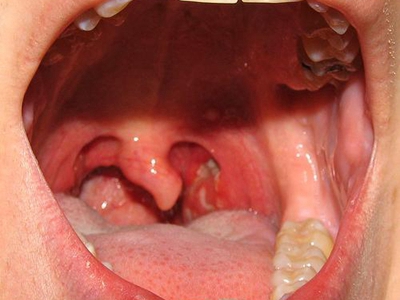

急性咽炎是咽黏膜、黏膜下组织的急性炎症,多累及咽部淋巴组织。此病可单独发生,亦常继发于急性鼻炎或急性扁桃体炎,常见于秋冬季及冬春季之交。患者主要症状为咽痛,检查可见咽部黏膜充血、水肿,需要多饮水,配合抗菌或抗病毒治疗。

急性咽炎起病较急,先有咽部干燥、灼热,继有明显咽痛,吞咽时尤重,有时可伴有发热、头痛、食欲减退和四肢酸痛等。检查可见口咽部黏膜呈急性弥漫性充血、肿胀,咽后壁淋巴滤泡隆起,表面可见黄白色点状渗出物。

可伴随悬雍垂及软腭水肿,下颌下淋巴结肿大、压痛。鼻咽及喉咽部亦可呈急性充血,严重者可见会厌水肿。